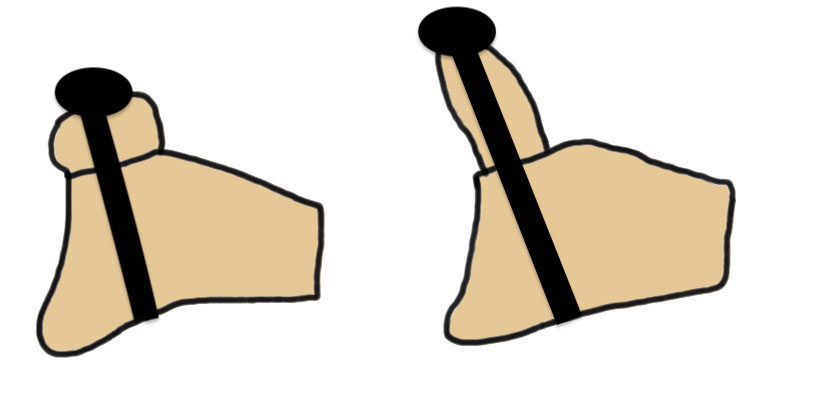

Traditional Latarjet v Congruent arc

- align concave inferior surface coracoid with medial concave glenoid

- graft is thinner in this position, making screw fixation more difficult

Traditional versus congruent arc Latarjet

- systematic review

- traditional latarjet: lower incidence fibrous or nonunion

- congruent arc: improved return to sport, recurrent instability and revision surgery for recurrent instability